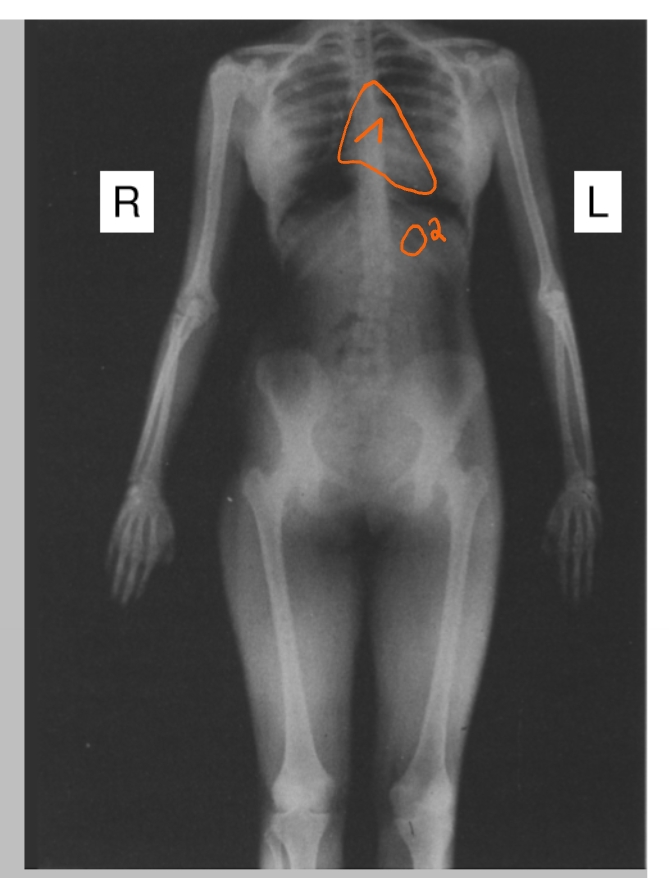

longen + ribben

in het midden: mediastinum

= structuren tussen de longen (bv. ook het hart)

vorm van het hart

luchtbel in de maag